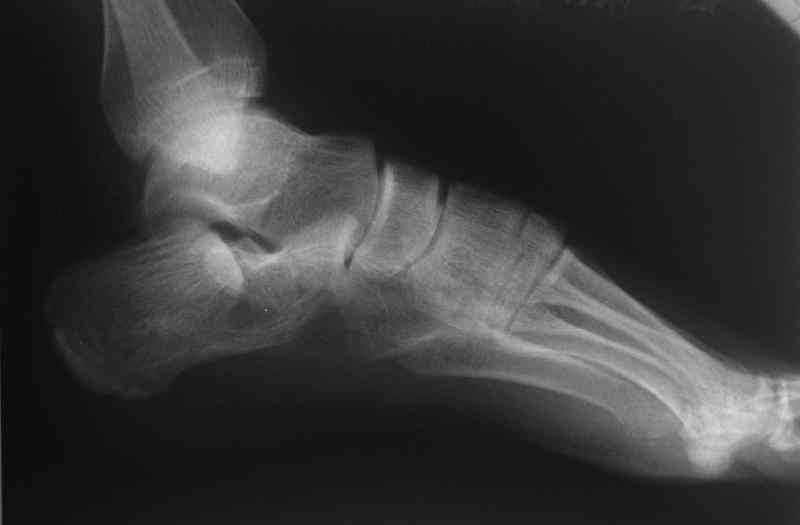

Если я правильно понял, вы хотели спросить: "Что делать с кистой, и как на этом фоне выполнять репозицию и фиксацию перелома?"

Я думаю, что для начала нужно выполнить КТ пяточной кости и определиться с границами полости. Не исключено, что отрывной перелом верхнего полюса бугра носит патологический характер (верхняя стенка кисты).

Думаю что это не киста, но КТ сделаем, спасиба.

Сустав похоже интактен, киста под вопросом,даже при наличии опыта остесинтеза пластиной, в данном случае выведение правильного угла и фиксация спицами более чем достаточно, да и намного спокойнее сон у хируга.